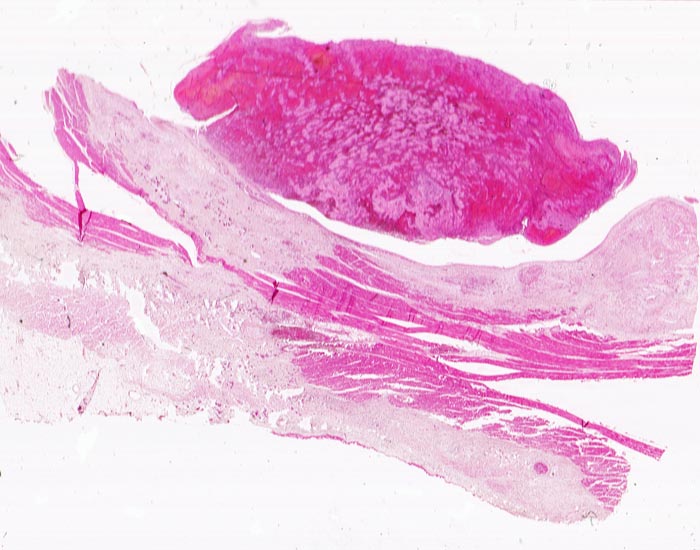

Das Präparat stammt von einer 90 jährigen Patientin. Makroskopie: schwere stenosierende Koronarsklerose mit frischem thrombotischem Verschluss des Ramus interventricularis anterior der linken Koronararterie. 8x9cm grosser akuter transmuraler anteroseptaler Myokardinfarkt.

Oben auf dem histologischen Präparat ist ein Querschnitt durch den Papillarmuskel zu sehen, unten auf dem Präparat ein tangentialer Schnitt durch die Myokardvorderwand